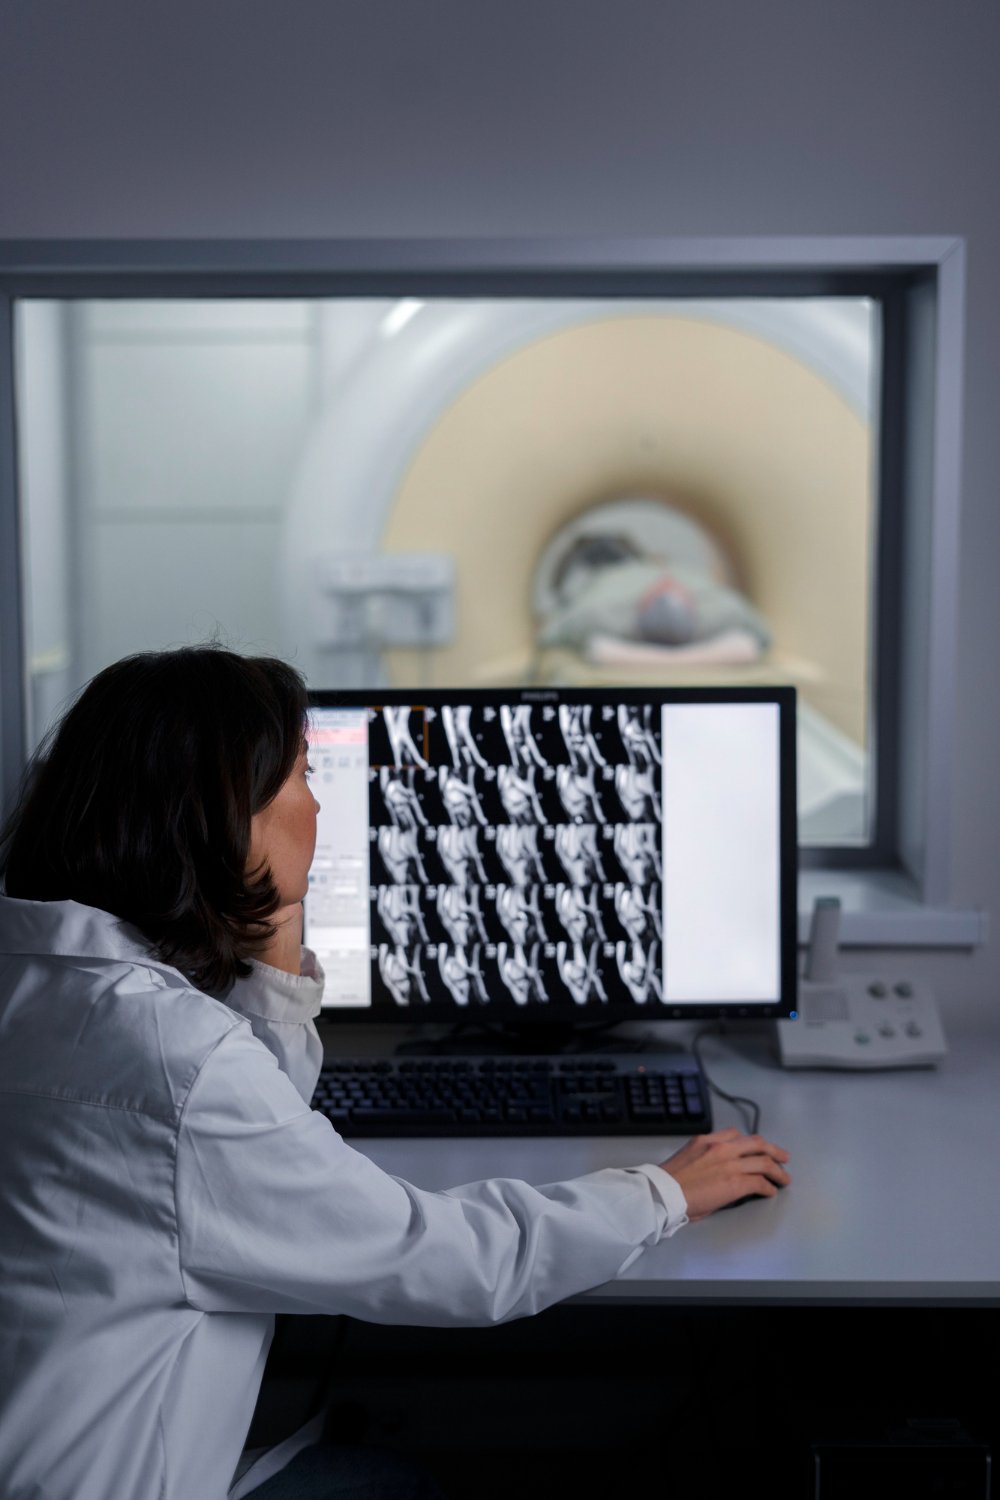

Imágenes en alta resolución para diagnósticos más exactos y confiables.

| TAC 1 REGIÓN SIMPLE |

| TAC 2 REGIONES SIMPLE |

| TAC 3 REGIONES SIMPLE |

| TAC 1 REGIÓN CONTRASTADA |

| TAC 2 REGIONES CONTRASTADA |

| TAC 3 REGIONES CONTRASTADA |

| TAC ABDOMINOPELVICO SIMPLE Y/O CONTRASTADA |

| ANGIO0TAC DE MIEMBROS INFERIORES |

| ANGIOTAC CEREBRAL |

| ANGIOTAC DE ABDOMEN |